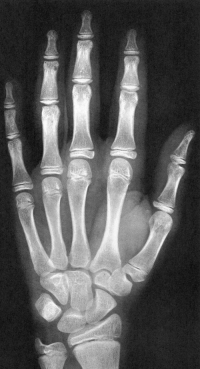

Sexo Masculino

Recém-Nascido

idade óssea - RN

Fonte: GREULICH, W.W. & PYLE, S.I.: Radiografic Atlas of Development of the Hand and Wrist. Stanford University Press, 2° edition, 1959.